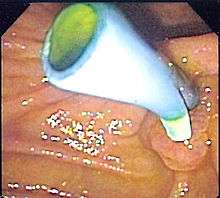

| Biliary stents provide bile drainage from the gallbladder, pancreas and bile ducts to the duodenum in conditions such as ascending cholangitis due to obstructing gallstones. | ![]() Endoscopic image of a biliary stent seen protruding from the ampulla of Vater at the time of duodenoscopy |